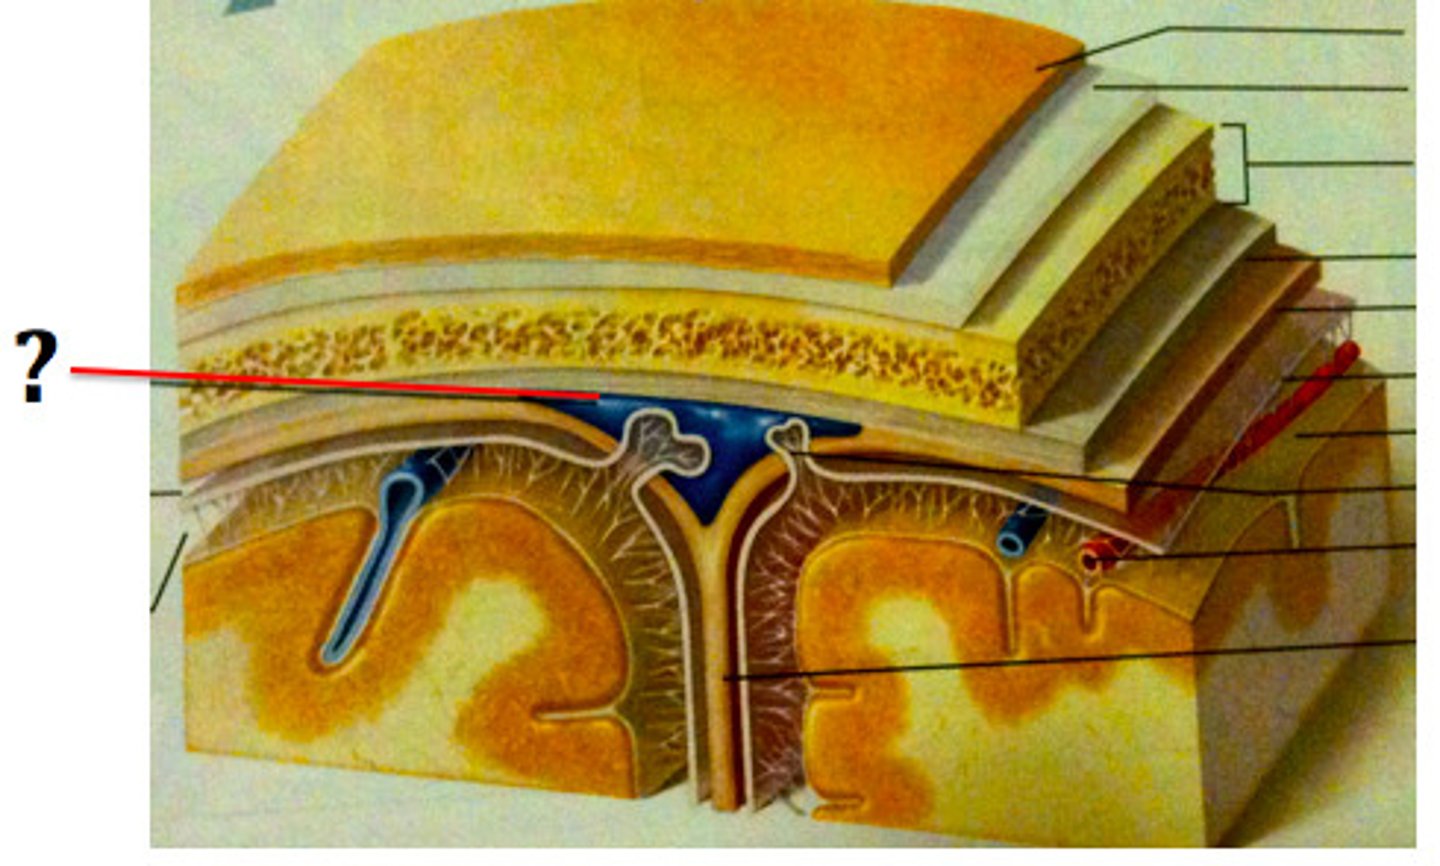

3 layers make up the meninges

dura mater, arachnoid mater, pia mater

dura mater

outer periosteal layer & inner meninges layer

periosteal and meningeal

two layers of dura mater

arachnoid

middle layer of meninges; weblike appearance that attaches it to deepest layer

arachnoid trabeculae

superior sagittal sinus

subdural space

space between dura mater and arachnoid mater

subarachnoid space

skin of scalp

arachnoid mater

pia mater

the delicate innermost membrane enveloping the brain and spinal cord.